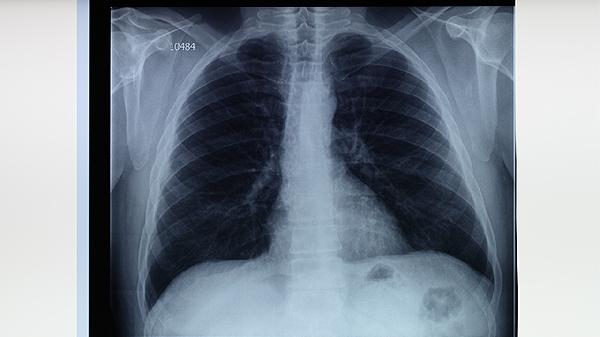

治疗期间需保持低盐高蛋白饮食,每日钠摄入控制在3克以内,适量补充鱼肉蛋奶等优质蛋白。恢复期可进行腹式呼吸训练改善肺功能,从每日2次、每次5分钟开始逐步增加。注意监测体重变化,若短期内增加超过2公斤需警惕积液复发。避免剧烈运动及突然体位变化,睡眠时可抬高床头30度减少夜间呼吸困难。定期复查胸片或超声直至积液完全吸收,结核性胸膜炎患者需完成全程抗结核治疗防止复发。